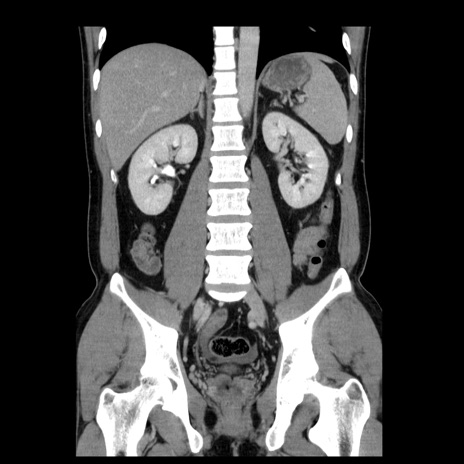

症例4(冠状断像)

【症例】30歳代男性

【主訴】腹痛、嘔吐

【現病歴】昨晩から突然の腹痛あり、その後嘔吐、軟便も出現。腹痛が改善しないため救急搬送となる。2日前にしめ鯖の食事歴あり。

【身体所見】意識清明、苦悶様、BP 135/90mmHg、BT 35.7℃、腹部:平坦、やや硬、心窩部〜臍部に自発痛、圧痛あり、筋性防御+、反跳痛-

【データ】WBC 8100、CRP 0.57